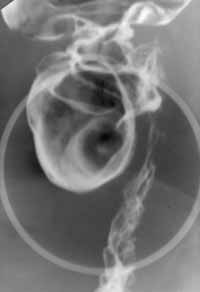

Случай аппендико-цекальной инвагинации.

Рис. 2. В центре дефекта наполнения депо контрастного вещества.